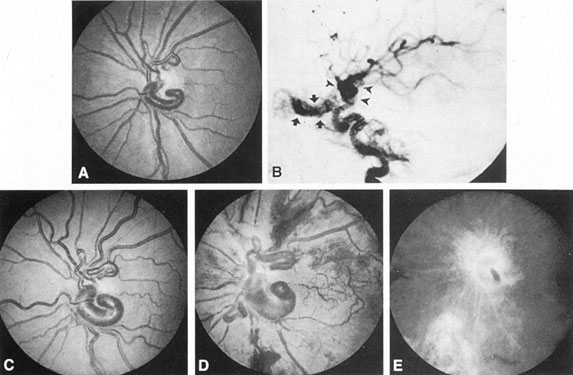

Carotid–cavernous fistulas are initiated by traumatic or spontaneous rents in the walls of the intracavernous internal carotid artery or its branches, with short-circuiting of arterial blood into the venous complex of the cavernous sinuses. The two cavernous sinuses are connected across the sphenoid, including the sellar floor and clivus, so that any signs and symptoms may be bilateral. The major anterior outflow structures of the cavernous sinus are the orbital veins, which become engorged, with secondary congestion of orbital soft tissues (Figs. 13 and 14). With raised venous pressure and lowered arterial perfusion, stagnant hypoxic changes also contribute to soft tissue swelling, some degree of ophthalmoplegia, and anterior segment ischemia.

Fig. 13. A: Right-sided carotid–cavernous fistula following head trauma. The right eye demonstrated pulsating exophthalmos with subjective and objective bruits. B: Close-up of the right eye with the lid elevated shows chemosis and arterialized conjunctival vessels. C: Left-sided carotid–cavernous fistula in a young man after a gunshot wound to the base of the skull. In addition to chemosis shown, there was a loud bruit over the forehead and involvement of left cranial nerves II through XII.

Fig. 14. Conjunctival vessels in two patients with carotid–cavernous fistulas. A: Large dilated veins in a patient with a major posttraumatic fistula. B: “Corkscrew” vessel tortuosity in a 55-year-old woman with a dural carotid–cavernous fistula.

In the fully evolved state, this syndrome includes lid swelling and orbital pain, varying degrees of pulsating exophthalmos, subjective or objective ocular or cephalic bruit, diplopia, engorged and chemotic conjunctiva, and raised intraocular tension. The fundus may show dilated veins without spontaneous pulsations, disc edema, retinal hemorrhages, venous stasis retinopathy or vein occlusions and, rarely, choroidal effusions.104–106 The ophthalmoplegia with carotid–cavernous fistulas is believed to be caused by enlarged muscles or to damage of cranial nerves within the cavernous or petrosal sinus.107 Enlarged extraocular muscles are demonstrable by ultrasongraphy in this form of venous stasis orbitopathy, also utrasonography uncovers reversal of flow in the superion ophthalmic vein.107 Sudden pain with increased swelling, followed by improvement, suggests thrombosis of the superior ophthalmic vein, an event that may be documented by orbital MRI108 or by standardized orbital echography. In addition, proptosis that improves on one side, only to increase on the opposite side, produces a picture of signs and symptoms more marked contralateral to the fistula.109

Anterior segment hypoxia may include protein flare and cells in aqueous, corneal edema, glaucoma, iris rubeosis, rapidly progressive cataract, and venous statis retinopathy, that is, an hypoxic eyeball syndrome. Lesser degrees of congestion with mild conjunctival arterialization (Fig. 15), ocular hypertension, and small abduction defect all hint at the slower flow, lower pressure situation that accrues usually spontaneously with dural circulation fistulas.104,106 Bruit is less likely.

Fig. 15. Dilated tortuous conjunctival vessels in a 63-year-old woman with a presumed dural carotid–cavernous fistula. She presented with a 2-week history of “red eye,” mild retroorbital headache, and double vision. On examination, a left sixth nerve paresis, 3 mm of proptosis, a faint orbital bruit, and slightly elevated intraocular pressure were found. All signs and symptoms resolved spontaneously in 6 weeks, while angiography was being contemplated.

Although the clinical constellation previously described implies the great likelihood of carotid–cavernous fistula, definitive diagnosis depends on complete angiographic evaluation with selective opacification of bilateral internal and external carotid arteries, and vertebral circulation. Prominence of the superior ophthalmic vein is frequently detected on CT scan and MRI, and less frequently extraocular muscle enlargement and lateral bulging of the cavernous sinus are seen by MRI.110 Standardized orbital echography regularly confirms enlargement of the superior ophthalmic vein and increased flow (Fig. 16),107,111 in both direct and indirect fistulas.

Fig. 16. Orbital ultrasonography. Transocular A-scans (left) and B-scans (right) in a carotid–cavernous fistula with dilated arterialized superior ophthalmic vein. Top left: Blurred spikes (arrow) within the dilated vessel indicate fast blood flow. Bottom left: Distinct spikes (arrows) from vessel walls, at low system sensitivity. Top right. Dilated superior ophthalmic vein (arrow), at low sensitivity setting. Bottom right: Cross-section of enlarged superior ophthalmic vein. (From Byrne SF, Glaser JS: Orbital tissue differentiation with standardized echography. Ophthalmology 90:1071, 1983.)

Therapy for carotid–cavernous fistula is directed toward relieving ocular symptoms, especially where visual loss is threatened, with the goal being thrombosis of the fistula with normalization of orbital hemodynamics. Various arterial ligatures, trapping procedures, controlled embolizations, and even direct intracranial attacks have been advocated, but the current trend indicates the great advance represented by intravascular closure using detachable balloon microcatheterization techniques (Fig. 17).106 Complications of these techniques include transient or fixed hemispheral dysfunction, cranial nerve palsies, field loss, and pseudoaneurysm formation.106,112 At least one case of acute angle-closure glaucoma was reported after transvenous embolization of a traumatic carotid–cavernous fistula necessitating emergency laser iridotomy.113 The complication was thought to arise from oculomotor palsy related to the coil pack within the ipsilateral cavernous sinus. However, complication rates are apparently low. In a series of 100 consecutive patients treated for direct carotid–cavernous fistula with detachable balloons, Lewis et al 114 reported an approximately 4% overall complication rate. Endovascular treatment of dural (indirect) carotid–cavernous fistulae is usually directed transvenously also using fibered platinum coils or, less often, liquid adhesive. A recent retrospective evaluation of 135 consecutive patients treated for dural carotidcavernous fistulae over a 15 year period by Meyers et al115 revealed low permanent morbidity of 2.3% and high 90% rate of clinical cure.

Fig. 17. A 32-year-old woman was accidentally shot in the right eye with a low-velocity missile. The initial recovery was excellent, except for loss of the right eye. Five days after the injury, left proptosis and bruit developed. Two weeks after the injury, she developed paralysis of the left sixth and fourth nerves, and visual acuity decreased to 20/400 (6/120) in her remaining (left) eye. An interventional neuroradiologic procedure was performed with complete return of function in the left eye. A: Left carotid arteriogram with immediate opacification of entire cavernous sinus (arrows). B: One-half second after (A) there was extensive filling of dural venous channels and orbital veins. C: Detachable flow-guided balloon (arrows) placed in the fistula under fluoroscopic control and opacified with contrast medium. D: Follow-up left carotid arteriogram after balloon (arrows) placement. The fistula was completely closed with preservation of carotid flow. (Courtesy of Dr. Charles Kerber.)